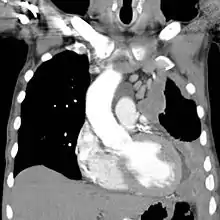

Left-sided mesothelioma (seen on the right of the image): chest CT

The most common diseases associated with chronic asbestos exposure are asbestosis (scarring of the lungs due to asbestos inhalation) and mesothelioma (cancer associated with asbestos).[9] Mesothelioma is an aggressive form of cancer and often leads to a life expectancy of less than 12 months after diagnosis.[108]